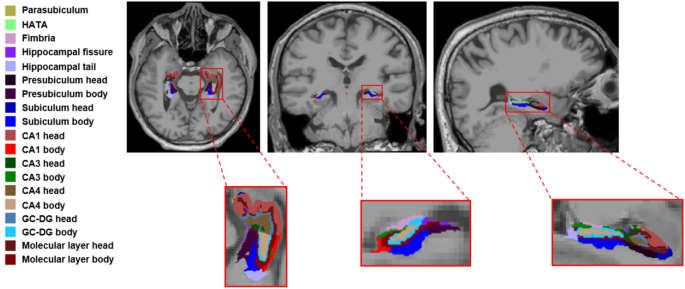

The hippocampal module within the FreeSurfer based on T1W was applied to perform hippocampal subfields segmentation. The hippocampus was divided into 19 subfields: hippocampal tail, subiculum head, subiculum body, parasubiculum, presubiculum head, presubiculum body, CA1 head, CA3 head, CA4 head, GC-DG head, molecular layer head, HATA, CA1 body, CA3 body, CA4 body, GC-DG body, molecular layer body, fimbria and hippocampal fissure (Fig. 1).

Hippocampal subfield segmentation. CA cornus ammonis, GC-DG granule cell layer of dentate gyrus, HATA hippocampus-amygdala transitional area.